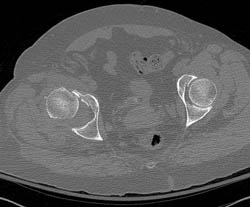

Dislocated Hip in Multiple Views